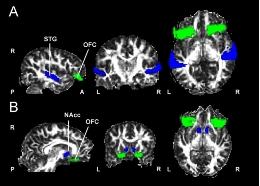

The study of the specific musical anhedonia determined that individual differences regarding musical rewards were related to the functional connectivity (different patterns of neuronal activation in different brain regions) in the auditory cortex, specifically the supratemporal auditory cortex, and a key area in the rewarding process, the ventral striatum. Thus, musical sensitivity depended on the work of these two areas together.

The results of the experiment show there is a relation between the white matter structures connecting the musical cortex and the activity in the reward system. According to Josep Marc-Pallarés, "the study shows musical sensitivity is related to white matter structures that connect, on the one hand, the supratemporal auditory cortex with the orbitofrontal cortex, and on the other, the orbitofrontal cortex with the ventral striatum".